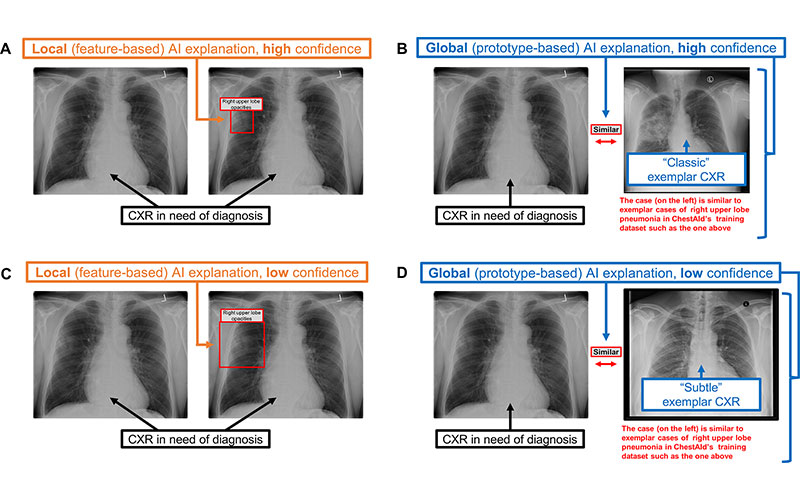

For each case, participants were presented with the patient’s clinical history, the AI advice and X-ray images. AI provided either a correct or incorrect diagnosis with local or global explanations. In a local explanation, AI highlights parts of the image deemed most important. For global explanations, AI provides similar images from previous cases to show how it arrived at its diagnosis.

“These local explanations directly guide the physician to the area of concern in real-time,” Dr. Yi said. “In our study, the AI literally put a box around areas of pneumonia or other abnormalities.”

Chest radiograph (CXR) examples of (A, C) local (feature-based) AI explanations and (B, D) global (prototype-based) AI explanations from a simulated AI tool, ChestAId, presented to physicians in the study. In all examples, the correct diagnostic impression for the radiograph case in question is “right upper lobe pneumonia,” and the corresponding AI advice is correct. The patient clinical information associated with this chest radiograph was “a 63-year-old male presenting to the Emergency Department with cough.” To better simulate a realistic AI system, explanation specificity was changed according to high (ie, 80%−94%) or low (ie, 65%–79%) AI confidence level: bounding boxes in high-confidence local AI explanations (example in A) were more precise than those in low-confidence ones (example in C); high-confidence global AI explanations (example in B) had more classic exemplar images than low-confidence ones (example in D), for which the exemplar images were more subtle.